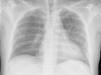

La radiografía simple de tórax evidencia ahora infiltrado intersticial bilateral (fig. 1). La analítica en UCI destaca por PaO2/FiO2<200, tiempo protrombina (INR) ratio 1,55, proteína C reactiva 249mg/L, sin leucocitosis.

La insistencia en inducir el esputo9, permitió en nuestro caso hacer el diagnóstico mediante la PCR. El aspecto de la radiografía de tórax, la gravedad del cuadro clínico y la terapia con AD, fueron consideraciones claves para incluir la cobertura específica del PJ en la terapia empírica inicial de este paciente.